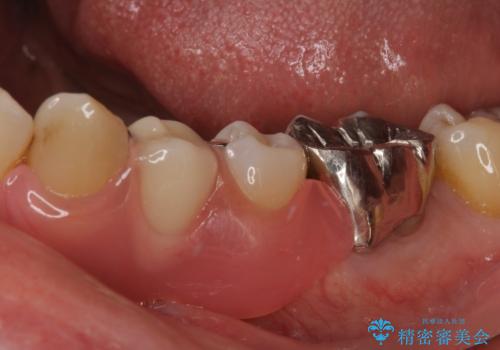

- 近医にて抜歯が必要と言われたとのことで来院された患者様です。

顕微鏡下で確認したところ、歯根に及ぶ破折線が認められたため、抜歯を行うこととしました。